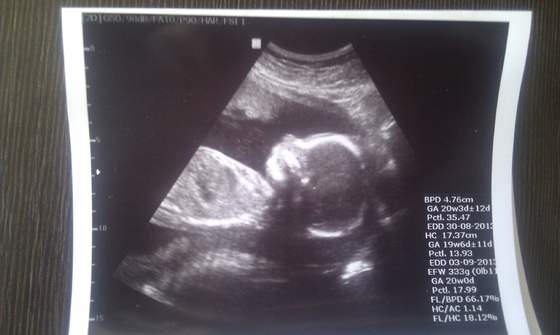

Melduje sie po wczorajszej wizycie. Mialam Usg polowkowe. Wszystkie pomiary wyszły dobrze. Dzidzius kręcił sie i nie chcial sie fotografowac wiec mam tylko jedno zdjęcie. Wyszedł mi stan zapalny w cytologi i dostalam globulki. Wysprzeglilam sie z 200 zł na wizytę plus dostalam badania do zrobienia ok.150 zł no i te globulki ok.40 zł. Wiec 400 zł wydane. Masakra! Najważniejsze ze synus zdrowy:) Oto fotka.

• IMAG0515.jpg

Synek przystojniak :) SUper, że z nim OK. A tak jak piszesz...kasy szkoda ale najważniejsze, że z maluszkiem dobrze :)